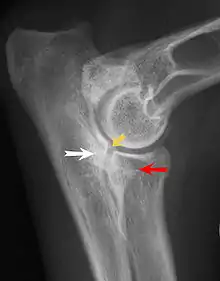

Na osteocondrite dissecante, o período normal de mudança de cartilagem para ósso no desenvolvimento da articulação falha ou está atrasada. A cartilagem continua a crescer e pode partir-se ou tornar-se necrótica. A causa é incerta, mas, possivelmente, inclui a genética, traumas e nutrição (incluindo o excesso de cálcio e diminuição da Vitamina C).[4] As lesões por osteocondrite dissecante são encontradas no cotovelo no epicôndilo medial do úmero. Condições específicas relativas à osteocondrite dissecante incluem a fragmentação do processo medial coronoid process da ulna e um ununited anconeal process da ulna. Todos os tipos de osteocondrite dissecante do cotovelo são geralmente encontrados em cães de raças grandes, com sintomas à partir dentre as idades de 4 a 8 meses. Os machos são afetados duas vezes mais frequentemente que as fêmeas. A doença geralmente afeta ambos os cotovelos (30 a 70% das vezes), e os sintomas incluem claudicação intermitente, inchaço das articulações, e rotação externa e abdução da pata.[5] Osteoartrite irá se desenvolver mais tarde na maioria dos casos.

Ununited anconeal process é causado pela separação da ulna do centro de ossificação do processo anconeal.[6] Processo medial coronoid process da ulna é causado por uma falha do coronoid process para unir-se com a ulna. Osteocondrite dissecante do epicôndilo medial do úmero é causada por distúrbios endocondral de fusão da epífise do epicôndilo medial, com a extremidade distal do úmero, que por sua vez, pode ser causado por avulsão da epífise.[7]

O diagnóstico é através de raios-x, artroscopia ou tomografia computadorizada. Em casos com significativa claudicação, a cirurgia é a melhor opção, especialmente com o ununited anconeal process. No entanto, o tratamento conservador é muitas vezes suficiente para os casos de medial coronoid process e osteocondrite dissecante da medial do úmero epicôndilo. Os cães são exercitados regularmente e medicados contra a dor, e entre as idades de 12 a 18 meses, a claudicação, muitas vezes, melhora ou desaparece. O controle de peso corporal é importante em todos os casos de displasia de cotovelo, e a prevenção de surtos de crescimento rápido em filhotes pode ajudar a prevenir a doença.